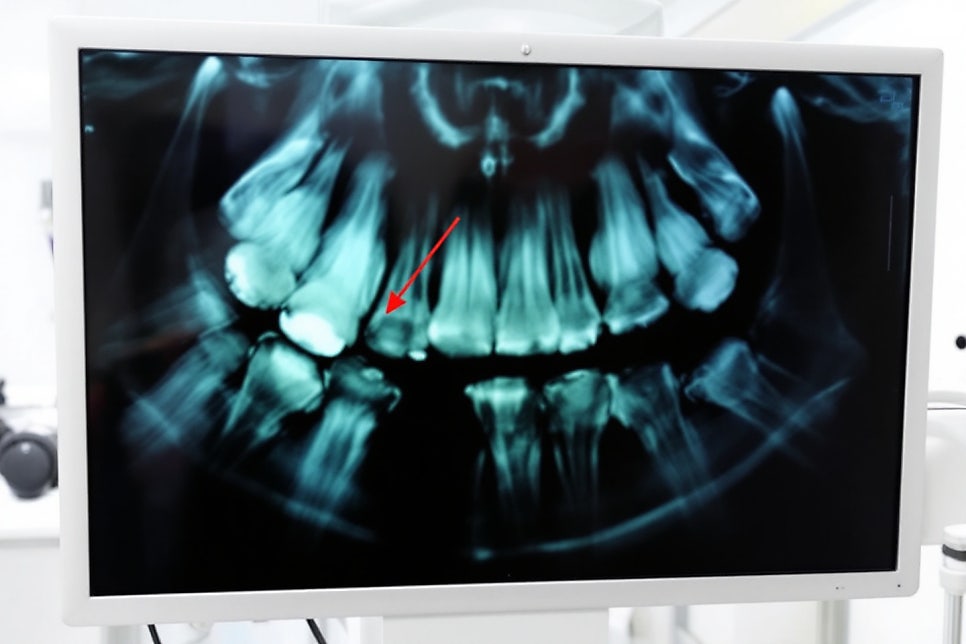

X-ray, 혈액검사, 교합검사 등에서 이상이 발견되지 않고 항생제나 소염진통제로 통증이 줄어들지 않는 경우가 있는데요

지속성 특발성 치조통(Persistent Idiopathic Dentoalveolar Pain, PIDP)은 치아와 치조골 부위에 명확한 원인 없이 지속적인 통증을 겪는 만성 통증 질환입니다. 통증은 깊고 둔하며, 주로 중년 여성에게서 더 흔히 발생하는 경향이 있습니다. PIDP는 임상적 검사와 방사선 검사에서 이상이 관찰되지 않기 때문에 '배제 진단'으로 불리며, 다른 모든 원인을 배제한 후 최종적으로 진단을 고려하게 되요.

PIDP의 진단 과정은 철저한 '배제 진단' 절차를 포함합니다. 이는 임상적 검사와 방사선 검사, 그리고 병력 청취를 통해 이루어집니다. PIDP 환자들은 종종 치과적인 다른 문제를 의심해 여러 검사를 받게 되지만, 명확한 원인을 발견하지 못하는 경우가 대부분입니다.

D. 임상 및 방사선 검사에서 정상이거나 국소적인 원인으로는 통증을 설명할 수 없는 경우